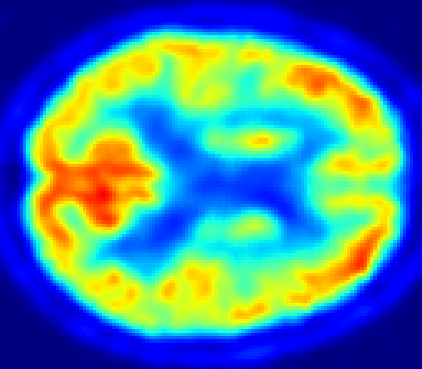

Looking at sample synthetic PET images in Fig. 3, it can be seen that all of the models are able to make reasonable predictions. The outputs of the U-PET and U-PET (no att.) look very similar and are smoothed compared to the input. The pix2pix predicts more details, which seem to be important for the discriminator. However, even though this model has finer predictions, the intensity values are worse compared to the U-PET and U-PET (no att.) as seen in Fig. 2; an example is given in Fig. 3 in the second row.

From a clinical perspective, the synthetic generated PET show a smoother version of the real PET images but keep the same pattern of FDG uptake, especially, hypometabolism in the respective brain areas. This backs up our hypothesis, that MRI contains information that correlates with the functional information of PET images. Moreover, the synthetic PET could be used as complementary visualization for physicians beyond the task of classification.